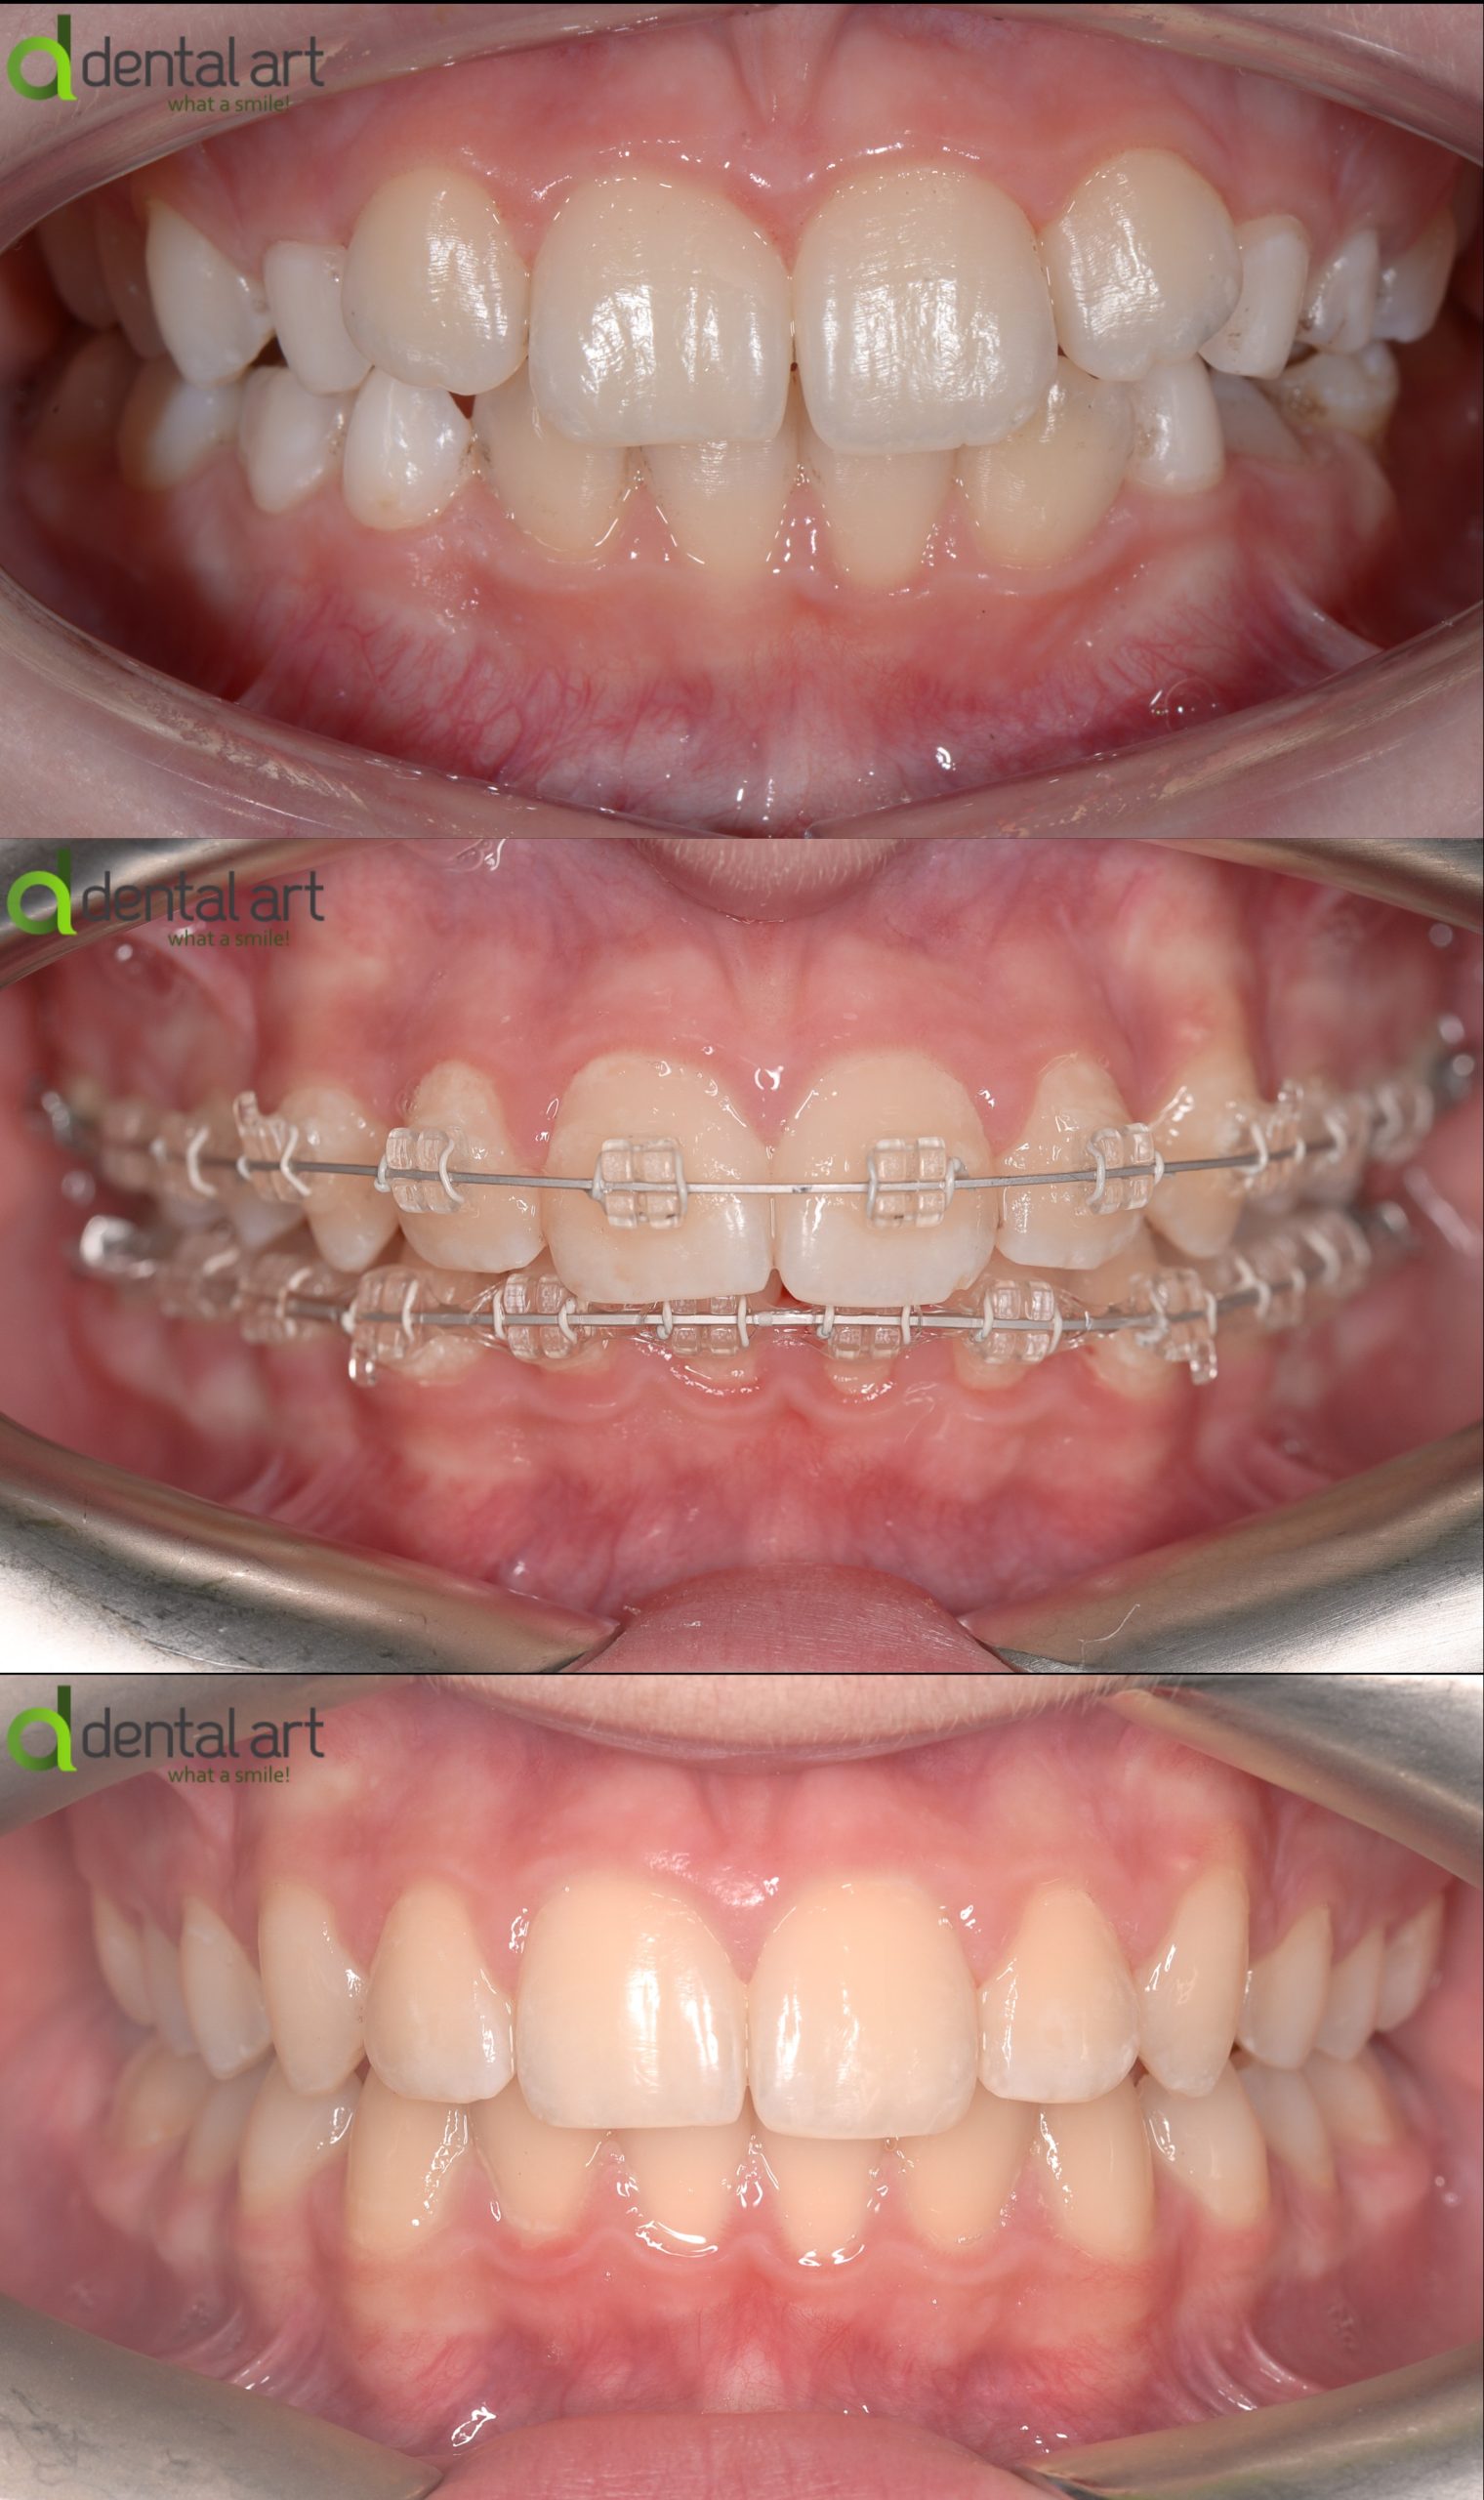

Aparat ortodontic fix - ceramic

Acest tip de aparat funcționează similar cu cel metalic, dar utilizează bracket-uri din ceramică, într-o nuanță apropiată de culoarea naturală a dinților. Este preferat de pacienții care își doresc un tratament ortodontic discret, fără a compromite eficiența.

Beneficii: estetică superioară, mai puțin vizibil

Dezavantaje: cost mai ridicat, bracket-urile pot fi mai fragile